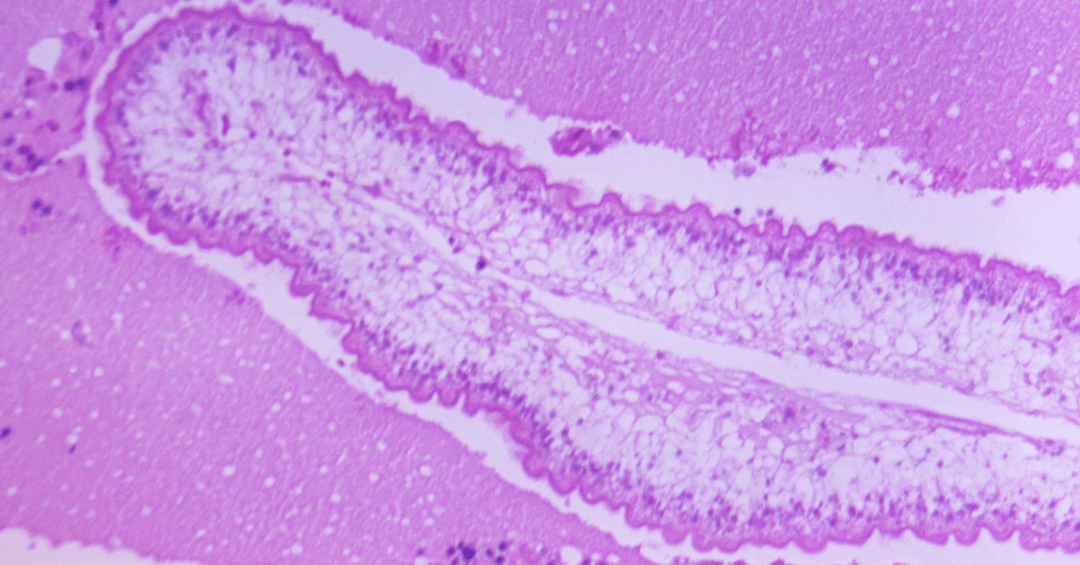

Aqui está o pulo do gato, o porquê dele ser tão eficiente! O Albendazol não brinca em serviço. Ele age de uma forma bem inteligente: o fármaco entra no parasita e começa a desestruturá-lo de dentro para fora. É como se ele “desligasse” a fonte de energia desses invasores.

Para ser mais técnica, mas sem complicação: ele impede que o parasita absorva a glicose, que é o açúcar essencial para a sobrevivência deles. Sem glicose, o parasita simplesmente não tem energia para nada, enfraquece e morre. Depois, é tudo eliminado pelas fezes. Simples, rápido e eficaz! Se quiser entender mais sobre a ação desse remédio antiparasitário para lombriga e outros, o UOL VivaBem explica em detalhes.